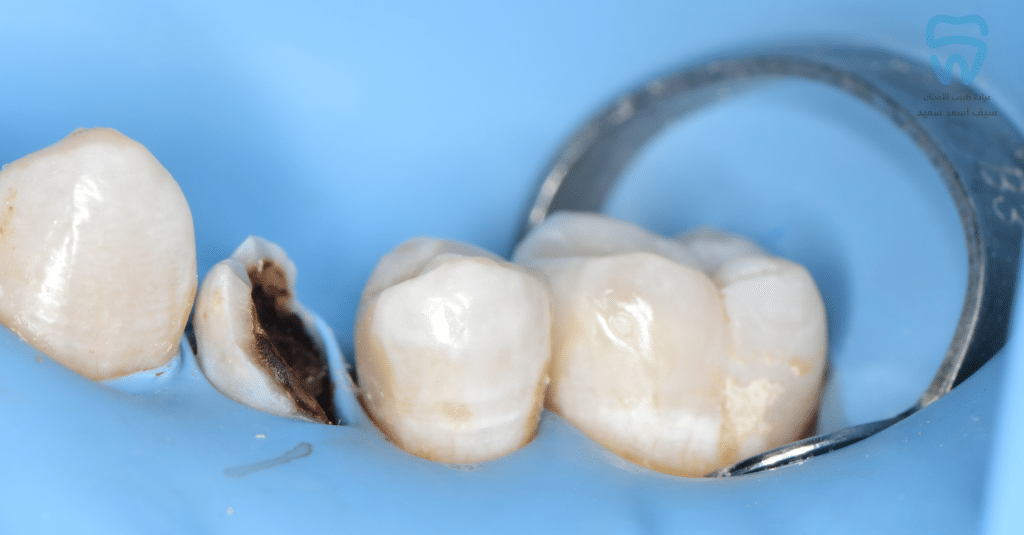

Metal ring of sectional matrix seated with Liquidam

Saddle and sectional bands supported by the modified ring